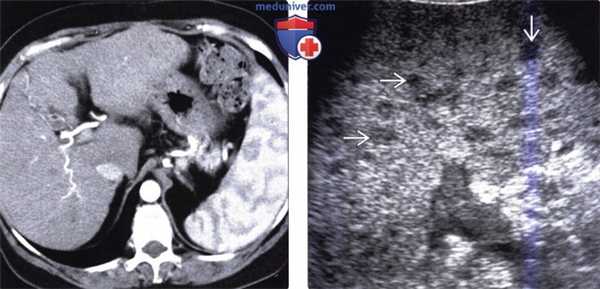

(Слева) На цветовой допплерограмме визуализируется единичный абсцесс селезенки с четкими контурами, гипоэхогенной центральной частью (некроз) и неравномерно утолщенной стенкой. Прилежащие к абсцессу участки паренхимы селезенки не выглядят патологически измененными. Обратите внимание на типичный а васкулярный характер абсцесса.

(Справа) На аксиальной Т1 МР томограмме с контрастным усилением у пациента с жалобами на боль в верхних отделах живота слева и повышение температуры тела определяется абсцесс селезенки с наличием множественных перегородок в структуре. При культуральном исследовании крови был выявлен стафилококк, пациент выздоровел на фоне приема антибиотиков.

(Слева) На аксиальной КТ с контрастным усилением у наркозависимого пациента 29 лет (вводящего наркотики внутривенно), у которого возникли множественные гнойничковые поражения кожи наряду с болью в животе и повышением температуры тела, определяется гиподенсный очаг в селезенке (абсцесс).

(Справа) На аксиальной КТ с контрастным усилением у этого же пациента определяются множественные абсцессы в печени. Во время эхокардиографии были также обнаружены вегетации на клапане аорты, обусловленные эндокардитом (не продемонстрированы).